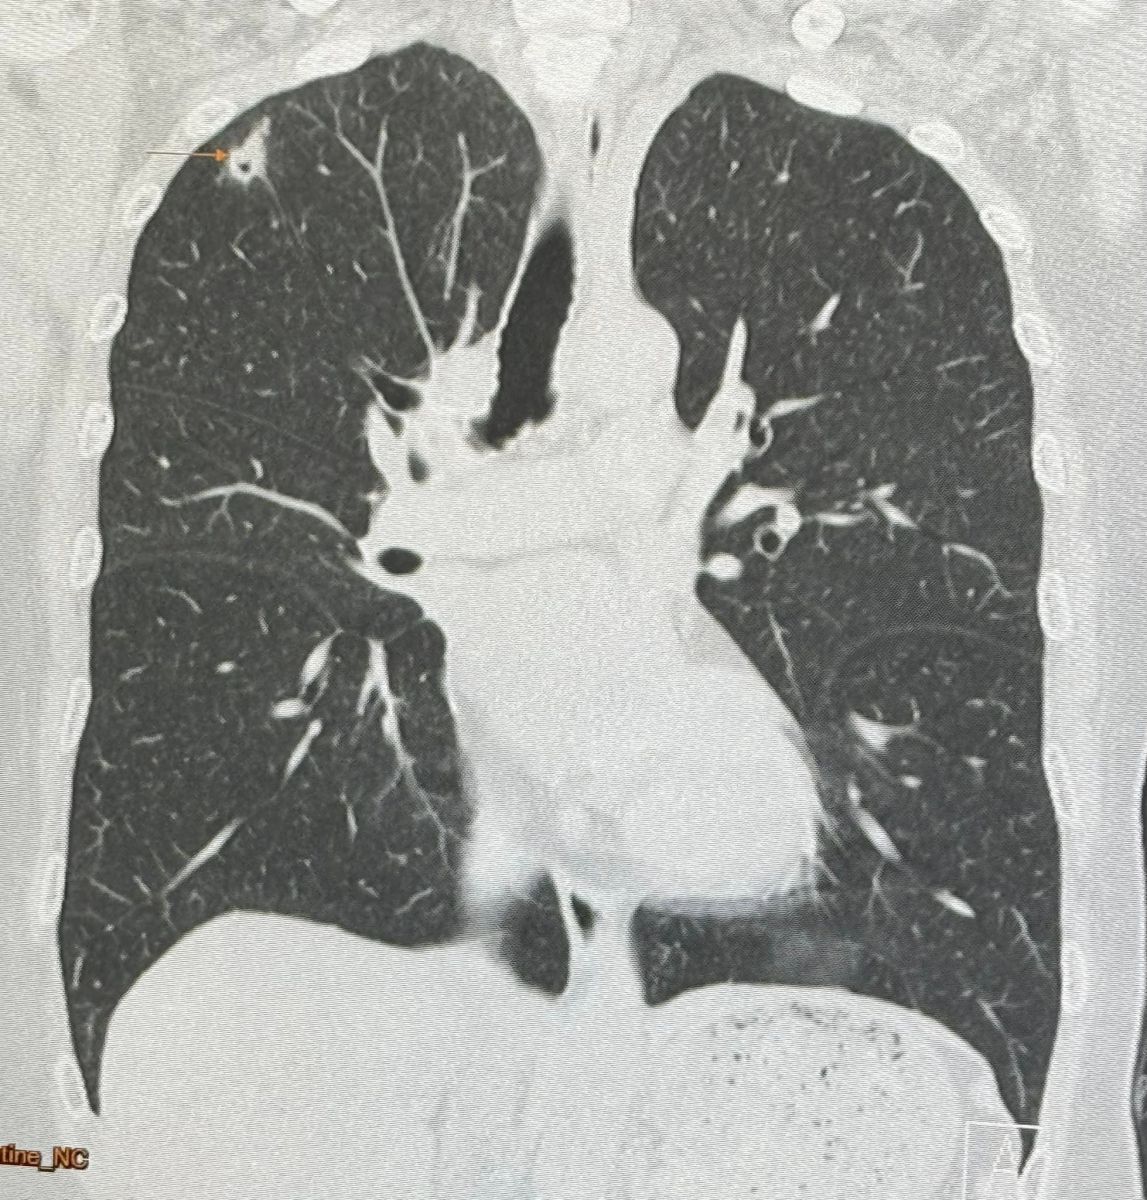

3 มิ.ย. 2567 นพ.มนูญ ลีเชวงวงศ์ ผู้เชี่ยวชาญด้านโรคระบบทางเดินหายใจ ได้โพสต์เฟซบุ๊กระบุว่า "ผู้ป่วยหญิงอายุ 52 ปี บ้านอยู่ กทม. ปกติแข็งแรงดี ไม่ไอ ไม่มีไข้ ไม่เบื่ออาหาร น้ำหนักไม่ลด ไม่ปวดหัว ไม่เคยสูบบุหรี่ ไม่มีโรคประจำตัว ไปตรวจร่างกายประจำปี วันที่ 12 พฤษภาคม 2567 เอกซเรย์ปอดพบก้อนเล็กๆเกิดขึ้นใหม่ที่ปอดขวากลีบบน เอกซเรย์ปอดก่อนหน้านั้น 1 ปีปกติ ทำคอมพิวเตอร์ปอดพบก้อนขนาด 0.9 × 0.9 × 1.7 เซนติเมตร เห็นโพรงอยู่ข้างในก้อนที่ปอดขวากลีบบน ตรวจเลือดไม่ติดเชื้อเอชไอวี ผู้ป่วยไปรับการผ่าตัดปอดเอาก้อนจากปอดขวากลีบบนออกที่โรงพยาบาลใกล้บ้านเมื่อวันที่ 22 พฤษภาคมเพราะสงสัยมะเร็งปอด ผลพยาธิวิทยาเป็นปอดอักเสบจากเชื้อราคริปโตคอคคัส ตรวจเลือดหาคริปโตคอคคัสแอนติเจนหลังผ่าตัด 4 วันให้ผลบวก titer 1:8 แพทย์เริ่มให้การรักษาด้วยยา fluconazole ผู้ป่วยมาขอคำแนะนำหลังจากนี้ควรทำอย่างไรต่อไป

ซักประวัติ มีนกพิราบอยู่แถวบ้านหลายตัว ให้อาหารนกพิราบประจำ ผู้ป่วยรายนี้หายใจสปอร์ของเชื้อราคริปโตคอคคัส นีโอฟอร์แมนส์ (Cryptococcus Neoformans) จากมูลนกพิราบเข้าไปในปอด ทำให้เกิดปอดอักเสบเป็นก้อนที่มีโพรงข้างใน โชคดีที่เชื้อราไม่ได้กระจายออกนอกปอดเนื่องจากร่างกายแข็งแรง มีภูมิคุ้มกันดี วางแผนให้ยาฆ่าเชื้อราฟลูโคนาโซลชนิดกินต่อไปประมาณ 6 เดือน แนะนำให้อยู่ห่าง และหลีกเลี่ยงให้อาหารนกพิราบ"